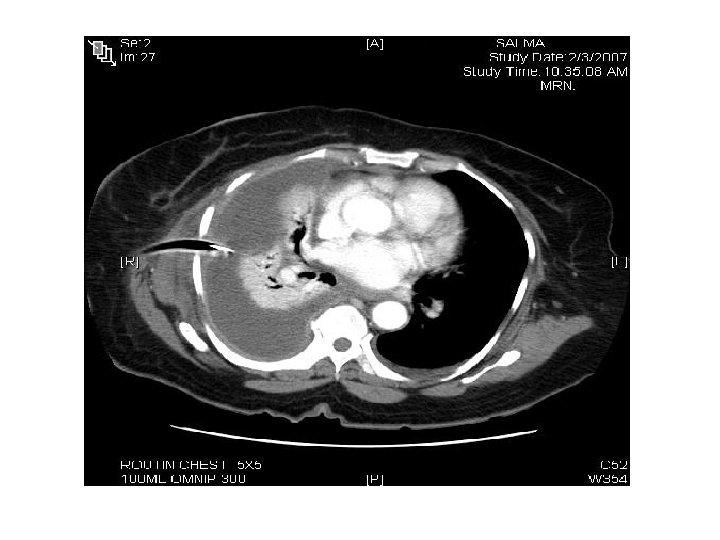

CT scan : infiltration , abcess formation , Lymph node

Tumors Left lower zone We say zone not lobe in X-Ray … because we can’t confirm the lobe except by other modality. . E. g. lateral Xray